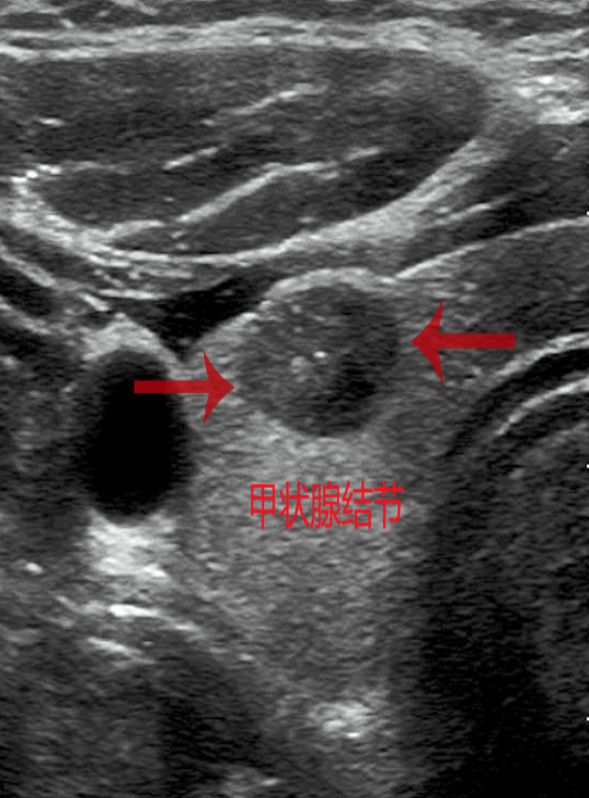

甲状腺结节,顾名思义就是甲状腺里长了小包块。根据包块的影像学特征分为囊性、囊实性和实性结节。根据病理类型分为增生性结节(增生活跃的甲状腺正常组织)、肿瘤性结节(良性或恶性)。